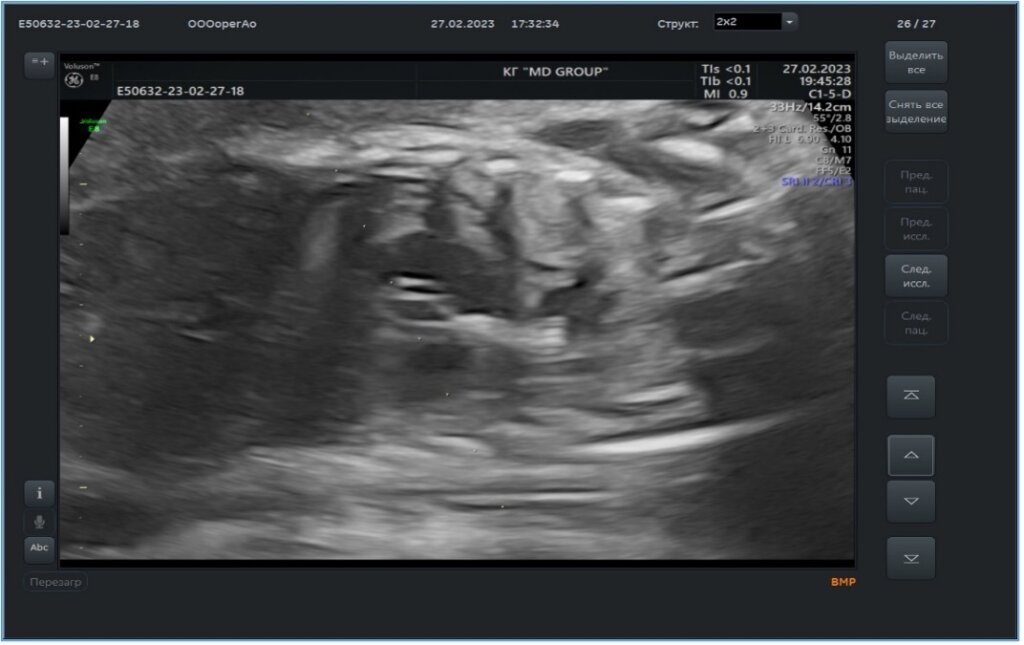

Согласно полученным данным, плод был признан операбельным. Для успешного проведения оперативного лечения важной особенностью является положение плода в полости матке. Его положение должно быть таким, чтобы грудная клетка ребенка была обращена к передней поверхности брюшной стенки матери, именно такое положение позволит беспрепятственно произвести катетеризацию левых камер сердца через все отделы (рис. 1).

После того, как положение плода признано соответствующим, мама вводится в наркоз. Акушер-гинеколог делает инъекцию седативного препарата в ножку ребенка, для чего под строгим контролем ЭхоКГ проводится специальная игла (Chiba) через все слои организма (передняя брюшная стенка мамы, матка, плацента). После введения в наркоз в некоторых случаях ребенок засыпая, может изменить свое положение, как было в нашем случае. Дважды, после седации ребенок поворачивался к передней брюшной стенке своей спиной, что делало невозможным проведение оперативного лечения. На третий раз, после введения в наркоз, положение плода осталось неизменным, что позволило провести оперативное лечение. Для этого специальная игла с мандреном диаметром 17-19G под контролем ультразвука устанавливается по направлению к верхушке левого желудочка и далее производится ее введение. Последовательно производится пункция передней брюшной стенки матери, матки, грудной клетки ребенка, после чего игла прокалывает верхушку левого желудочка строго в направлении клапана аорты. Игла заводится не более чем на 1/2 расстояния от верхушки левого желудочка до клапана аорты (рис.2).